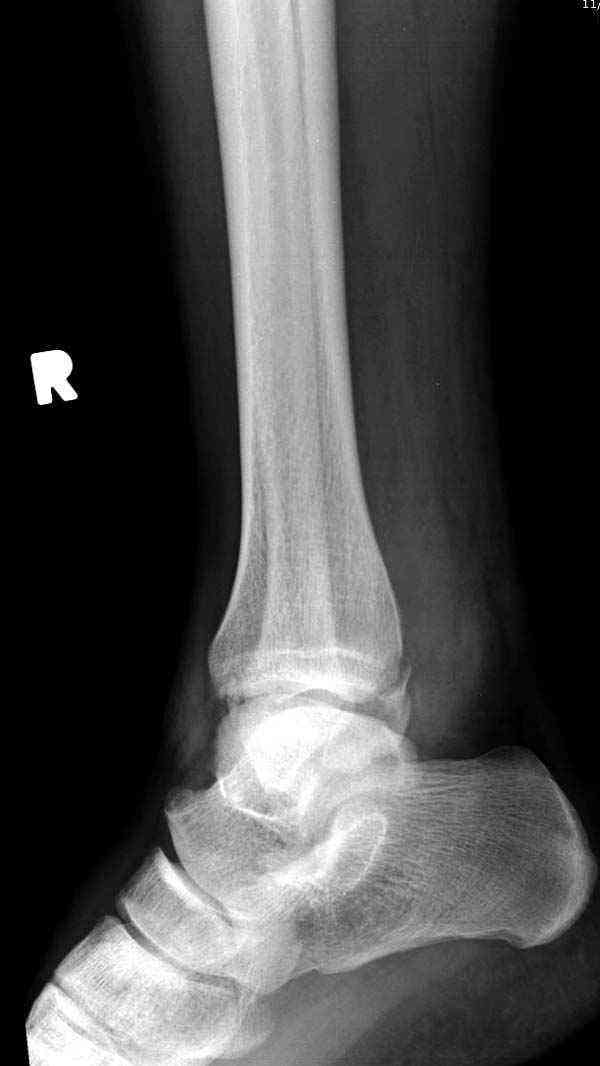

Случай прошлого года:пациентка-молодая ,крупная женщина ,30лет.Травма в начале апреля 2009г-пронационный перелом лодыжек с подвывихом стопы.Ко мне обратилась через 35 дней,прооперирована 22.05.2009г.Внутренняя лодыжка фиксирована по Веберу,наружная реконструктивной пластиной с наложением болта-стяжки.Иммобилизация "сапожок" в течении месяца,затем пригипсовано "стремя".Гипс снят 10.07.2009г

Достаточно быстрое восстановление функции.В октябре 2009г-почувствовала боль,в области рубца над гайкой открылся свищ.На Р-граммах-консолидация переломов и смещение гайки по стяжке.10.11.2009г-конструкции удалены,санация,заживление ран.В настоящее время пациентку ничего не беспокоит.На операции-раскручивание гайки-болталась на конце стяжки.Вопросы:какой механизм раскручивания и что я неправильно сделал?Свои версии:1)в области синдесмоза успела образоваться рубцовая ткань,которая при движении в суставе"пружинила",поскольку голеностопный сустав является спиральным, то и биомеханика подобна кривошипному механизму.2)Реконструктивная пластина не "реконструировалась" по форме лодыжки.Наложил,как есть.То есть подпружинивала сама пластина.Ну,это мои догадки.Что нужно,чтобы избегать впредь таких,пусть и не "страшных"осложнений:Рассверливать через лодыжку область синдесмоза?Ставить шайбу-гровер?Тщательно моделировать пластину?Прилагаю сравнительные снимки-сразу после операции и перед удалением конструкции.

Визуально никаких вопросов по репозиции не было.Да и на основании чего сомнения,что наружная лодыжка не полностью репонирована или прорезалась проволка ???Я не вижу...Снимок после репозиции справа.

Нет первичных снимков, перелом очень низкий и под большим сомнением диагноз разрыва синдесмоза. Медиальная сторона отрепонирована на "хорошо" и, по-видимому, прорезание проволоки произошло во время операции. Без снимков трудно судить о высоте малоберцовой, а лодыжка находится в варусе. Лагирование получилось, но возле тонких шурупов передне-задний шуруп выглядит немного тяжеловато.